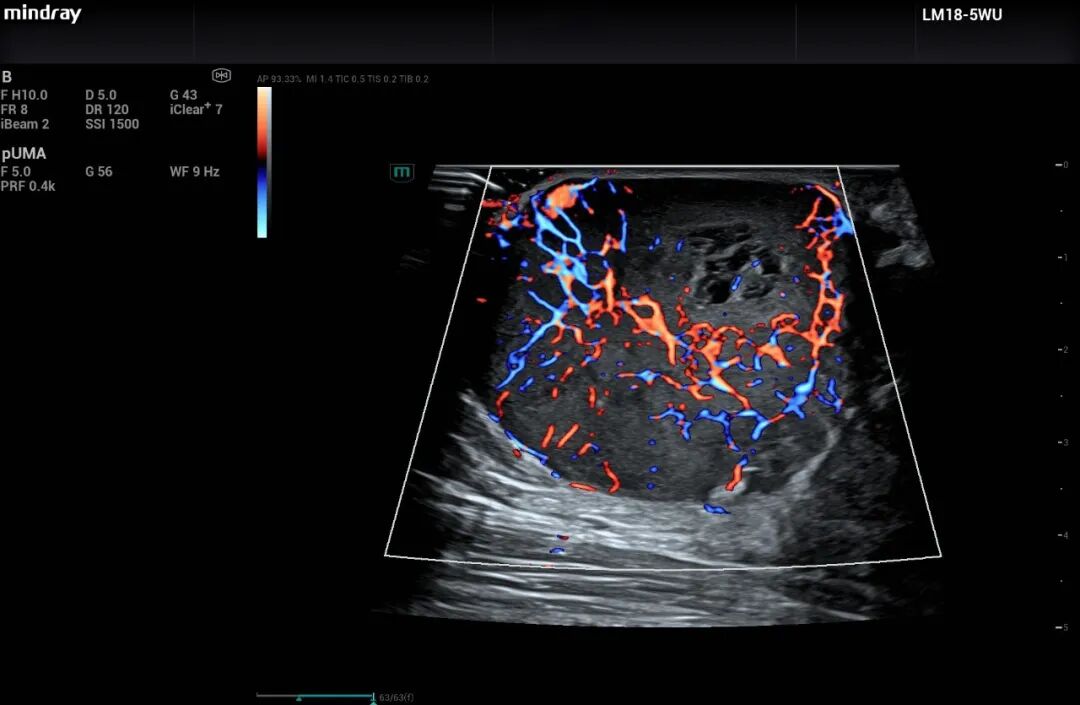

面对不同国家在临床方面的法规差异,迈瑞Resona A20系列超声以超声新技术完成了对部分需求的替代。以泰国为例,由于医疗法规限制,部分场景下不允许使用超声造影剂。针对这一现实挑战,迈瑞Resona A20搭载的UMA超微血管成像技术,能够在无需造影剂的情况下,清晰显示微米级血管形态和低速血流,为临床诊断提供了全新视角。

Resona A20的UMA超声图像

一位泰国超声专家在体验后评价道:“在不可使用造影剂的条件下,迈瑞的UMA技术提供了如同‘无造影剂的造影成像功能’,让我们看清了微米级血管形态。”